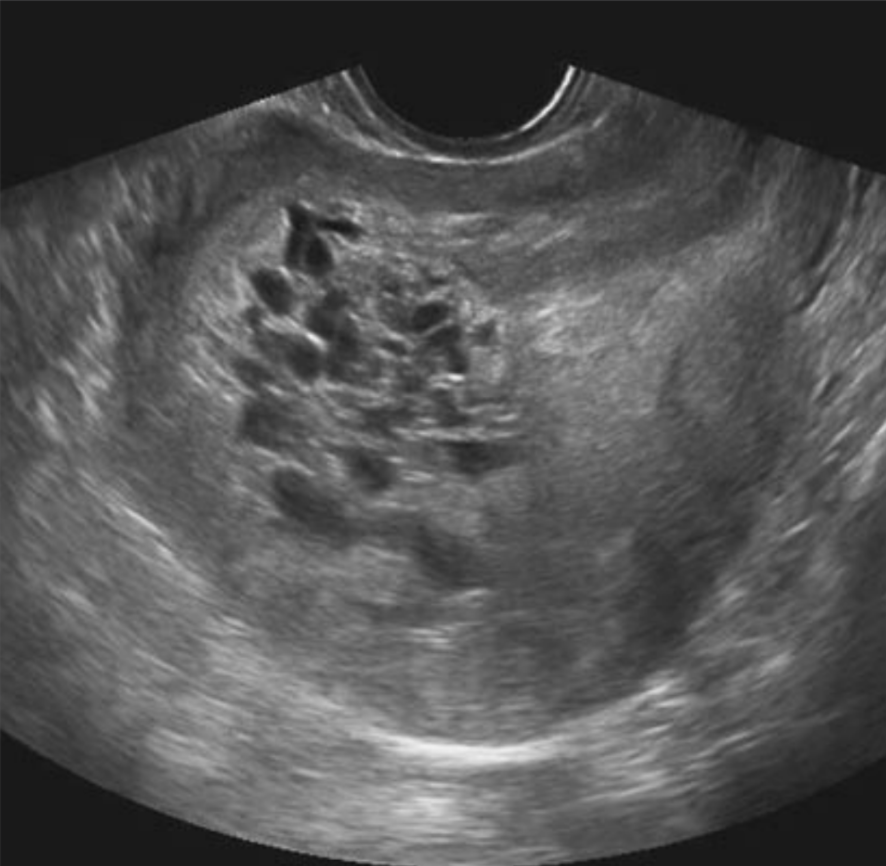

A 30-year-old primigravida complains of vaginal bleeding, pain in the abdomen, and vomiting. The uterus is enlarged, soft, and non-tender. Based on the ultrasound findings, what is the most likely diagnosis?

Explanation: ***Hydatidiform mole*** - Classic presentation of **vaginal bleeding**, **hyperemesis gravidarum** (severe vomiting), and **enlarged soft uterus** in a primigravida strongly suggests molar pregnancy. - Ultrasound shows characteristic **"snowstorm" appearance** with grape-like vesicular pattern and absence of fetal structures. *Missed abortion* - Features **retained dead fetus** with **closed cervix** and **absence of cardiac activity** on ultrasound, not the snowstorm pattern. - Typically presents with **minimal bleeding** and **cramping pain**, with uterus smaller than expected for gestational age. *Blighted ovum* - Shows **empty gestational sac** without embryonic structures on ultrasound, lacking the vesicular pattern of molar pregnancy. - Usually presents with **mild bleeding** and **cramping**, without the severe vomiting seen in this case. *Ectopic pregnancy* - Occurs when pregnancy implants **outside the uterine cavity**, most commonly in **fallopian tubes**. - Presents with **severe unilateral pain**, **amenorrhea**, and potential **hemodynamic instability**, not an enlarged soft uterus.